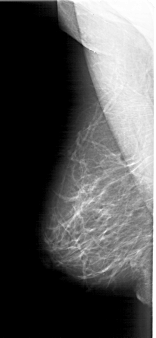

A_1770_1.RIGHT_MLO

LEFT_MLO LINES 6406 PIXELS_PER_LINE 2956 BITS_PER_PIXEL 12 RESOLUTION 43.5 NON_OVERLAY